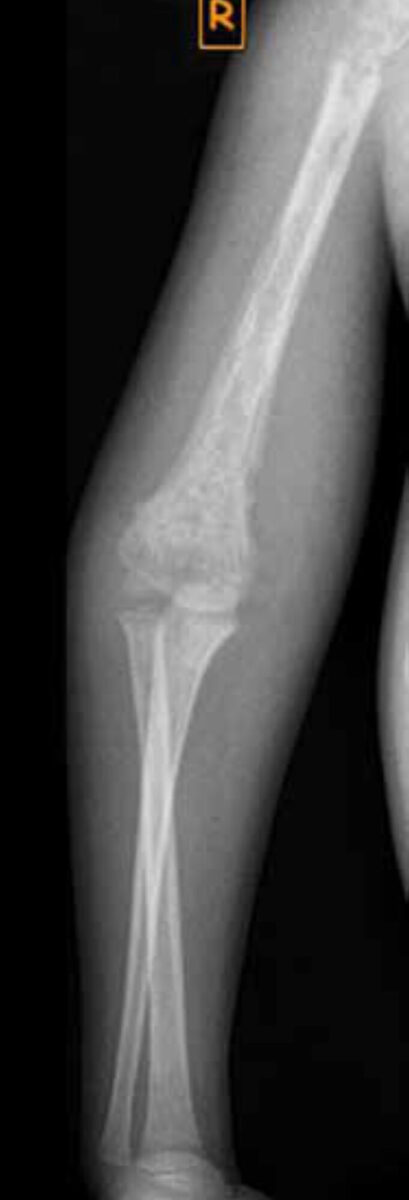

During physical examination he looked ill; the temperature was normal. His right upper arm and upper leg were swollen and there was a healed scar in the middle of the dorsal side of the upper arm. Passive and active movement of both extremities were very painful and limited. The right leg was shortened. The erythrocyte sedimentation rate (ESR) was 70 mm/hour; C-reactive protein (CRP) and white cell count (WCC) were not measured. X-rays showed evidence of severe osteomyelitis in both femur and the right humerus. There was an epiphysiolysis of the right femoral head; the caput was intact but there was a spiral fracture of the proximal femur (x-rays 1 and 2).